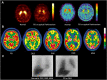

The early differential diagnosis of Parkinson disease and atypical parkinsonism is a major challenge. The use of single photon emission computed tomography (SPECT)/positron emission tomography (PET) molecular imaging to investigate parkinsonism is a fast-developing field. Imaging biomarker research may potentially lead to more accurate disease detection, enabling earlier diagnosis and treatment. This review summarizes recent SPECT/PET advances in radiopharmaceuticals and imaging technologies/analyses that improve the diagnosis of neurodegenerative parkinsonism. We are currently witnessing a turning point in the field. Integrating molecular imaging as a diagnostic technique represents an opportunity to reassess the strategies for diagnosing neurodegenerative parkinsonism. ANN NEUROL 2021;90:711-719.